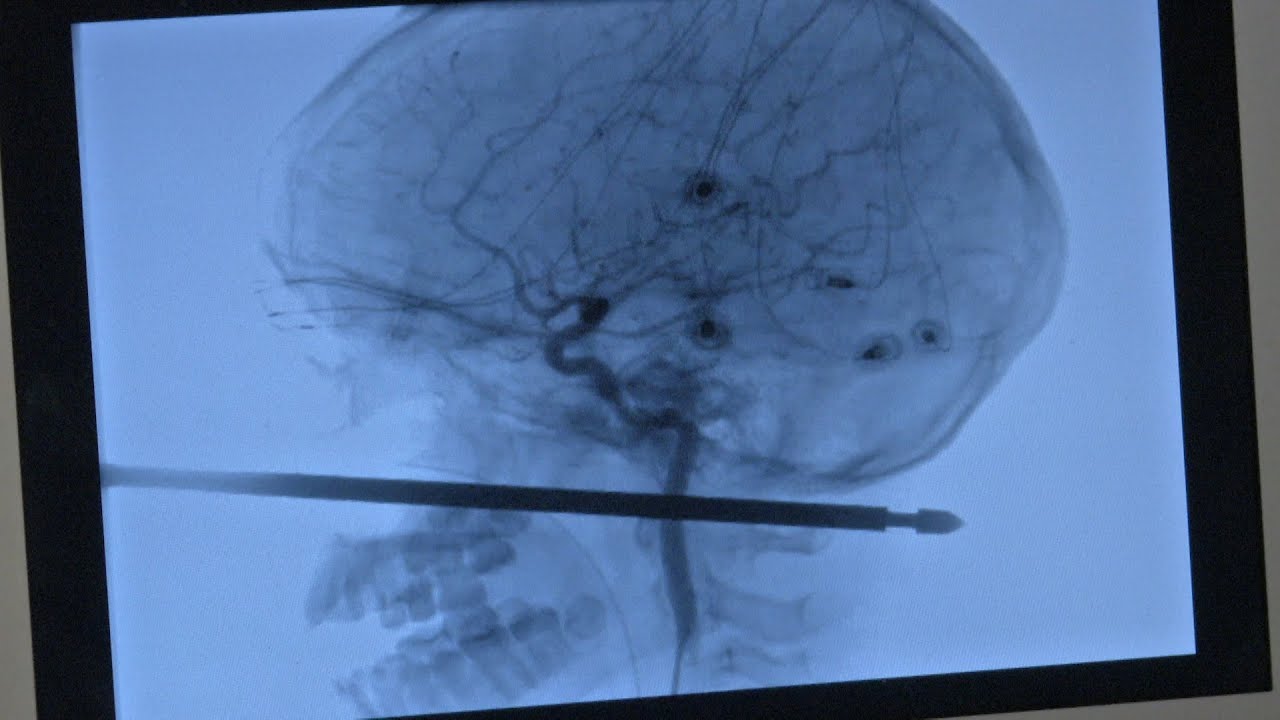

Well, maybe if your face landed on an upright meat skewer that you’d jammed in the ground earlier, and it went all the way through your head and out the other side. Yes, agreed, that would be how things could get worse.

This is what happened to Xavier Cunningham, a 10-year-old (yep) from western Missouri.

A big old meat skewer went right through his goddamn head, and - we didn’t tell you this part - he then got stung by hundreds of wasps, while there was a meat skewer sticking out of his skull, covered in wasps, meat skewer in head, wasps and meat skewers, stung and impaled, MEAT SKEWER THROUGH THE NOGGIN, STINGS IN THE SKIN. What the hell.

But back to Xavier - somehow, the humongous pole that plonked right into his bin missed everything important and just nipped straight through out the back of his neck - like, not ideal, but could have been so much worse.

Koji Ebersole, director of endovascular neurosurgery at the University of Kansas Health System, said:

“We were worried about how hard to pull the device because it was buried so deeply, [but] after an inch or so, it started to move more freely.”

“The depth that thing passed through the skull and this child being awake and talking and alive […] It’s flabbergasting.”